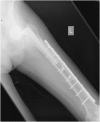

We report an 85-year-old patient with severe osteoporosis who had suffered from multiple episodes of periprosthetic fracture of the femur. Revision fixation with long-spanning cable plate for bisphosphonate-induced atypical periprosthetic femoral fracture was performed. Nonunion and implant failure occurred at 16 months requiring revision surgery using long-stem femoral prosthesis with cable-plate fixation. To further facilitate bone healing, allograft and bone morphogenetic protein (BMP) were added. Eventually bone union was achieved after one year.